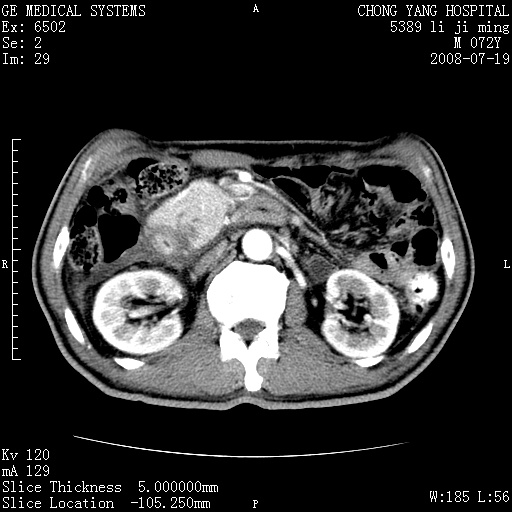

以下是引用zjzjr在2008-7-19 20:57:00的发言:[br]胰头增大,边缘模糊,周围可见渗出影,右侧肾前筋膜增厚.支持胰腺炎.

以下是引用yangyudong333在2008-7-20 6:56:00的发言:[br]胰腺增大尤以胰头明显,边缘模糊,周围可见渗出影,右侧肾前筋膜增厚,肠管於涨.支持胰腺炎

以下是引用不学无术在2008-7-19 23:15:00的发言:[br]胰腺增大尤以胰头明显,边缘模糊,周围可见渗出影,右侧肾前筋膜增厚,肠管於涨.支持胰腺炎